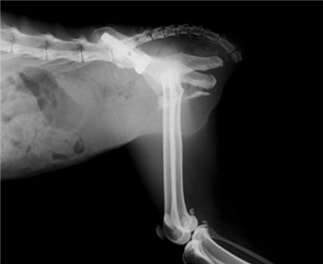

ペルシャ猫 11ヶ月齢 雄

他院にて左大腿骨遠位の成長板骨折(salter-harrisⅠ型)が認められており、治療相談を目的として来院。当院にて、キルシュナーワイヤーを用いたピンニングにより骨折部位の整復を行いました。術後の経過は良好で、現在も経過観察中です。

術前レントゲン